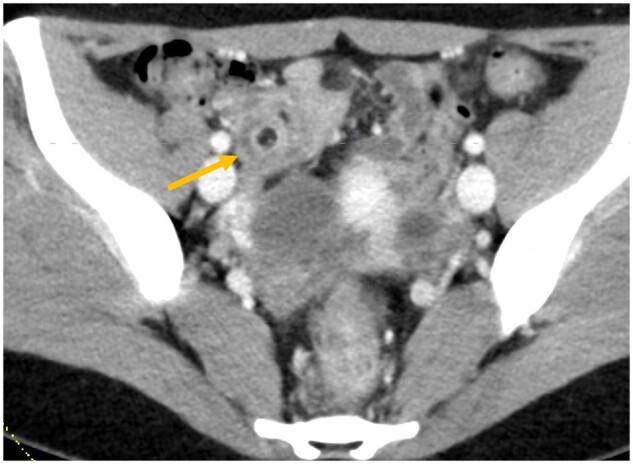

阑尾肠套叠是一种罕见疾病,其特征是部分或整个阑尾伸缩或内陷到盲肠或阑尾本身。由于其罕见性、非特异性症状以及医生缺乏认识,阑尾肠套叠的诊断具有挑战性。我们报告了一例年轻女性因子宫内膜异位症引起阑尾肠套叠并伴有反复腹痛的病例,该病例最初在 CT 扫描和腹腔镜检查中被漏诊,最终在 CT 肠造影检查中被确诊。

Appendiceal intussusception is a rare condition characterized by the telescoping or invagination of a portion or the entire appendix into the caecum or within the appendix itself. Diagnosing appendiceal intussusception can be challenging due to its rarity, non-specific symptoms, and lack of awareness among physicians. We present a case report of appendiceal intussusception caused by endometriosis presenting with recurrent abdominal pain in a young female that was initially missed on CT scan and laparoscopy and eventually diagnosed on CT enterography.